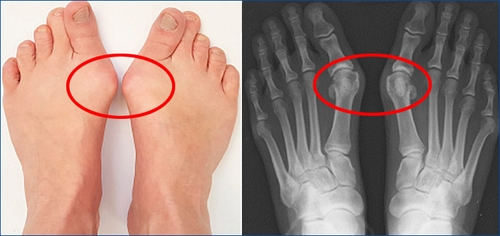

6. 발가락 변형(예: 무지외반증)

무지외반증과 같은 발가락의 변형은 발바닥 앞쪽에 비정상적인 압력을 가하여 통증을 유발할 수 있습니다.